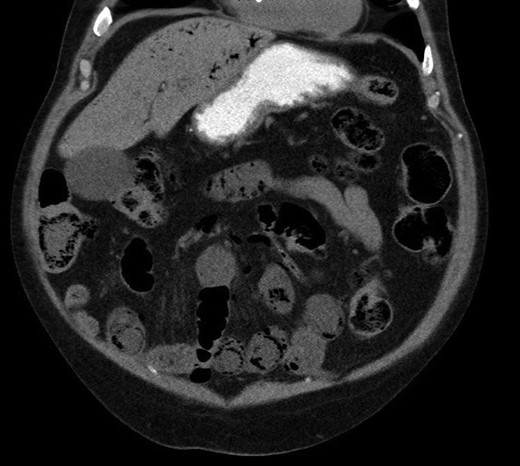

A CT with mesenteric angiogram was organized as the patient’s pain had not resolved despite him opening his bowels post enema. The CT imaging revealed some mildly distended and thickened bowel loops in the distal jejunum and ileum, with gas in the bowel wall (PI) and extensive gas tracking through the portal vein and into the hepatic venous tree (Fig. 1). No other organ or vascular abnormality was noted.

Pneumatosis intestinalis in jejunal and ileal loops, with hepatic venous gas evident.